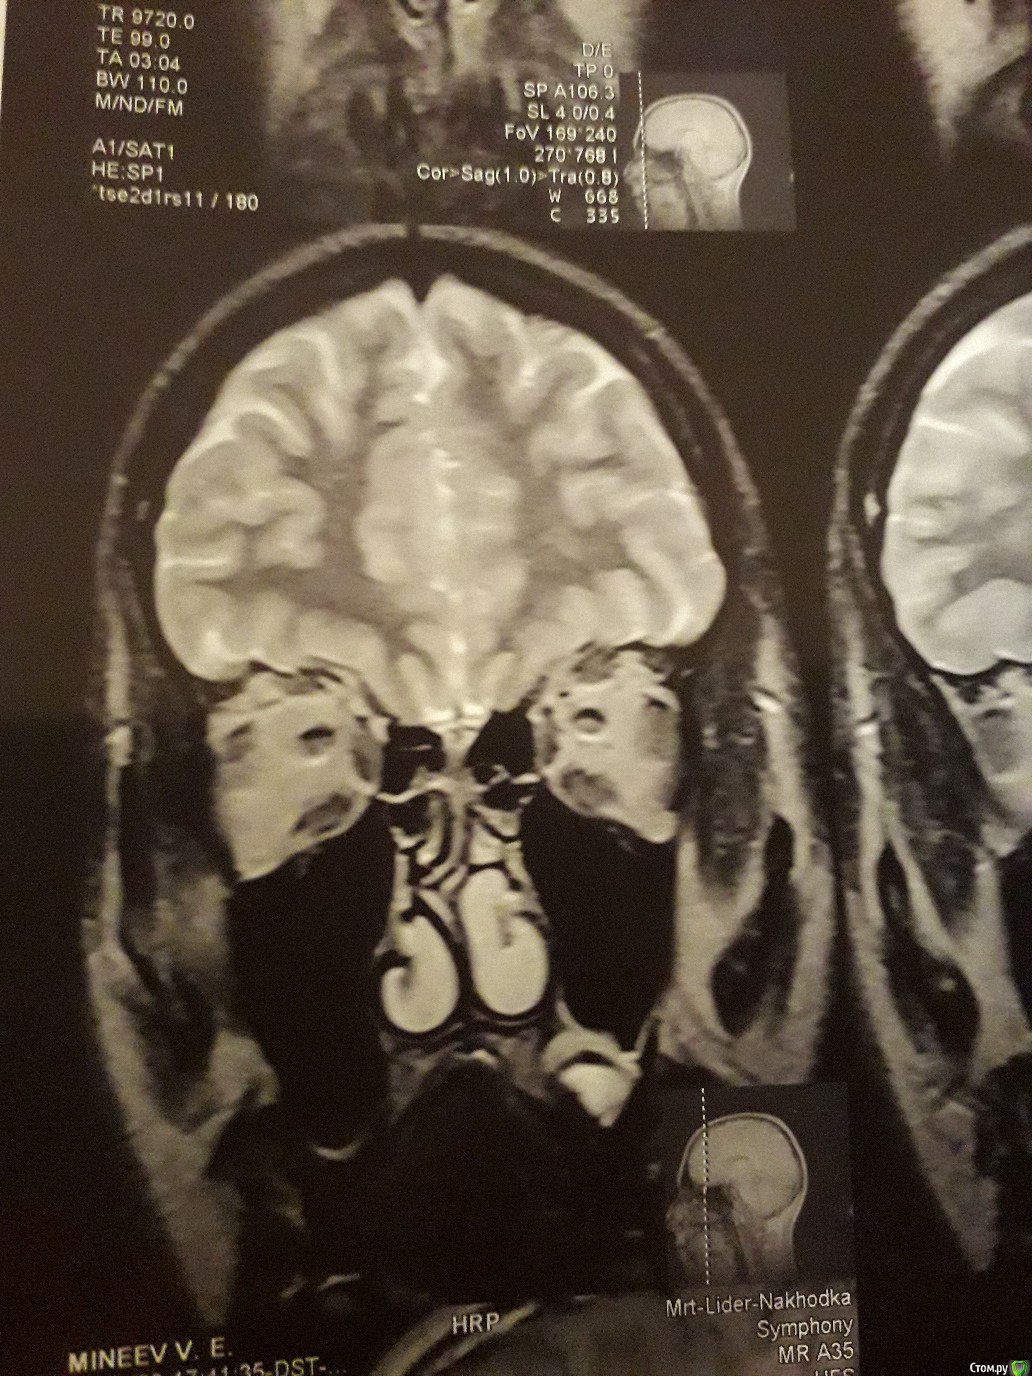

Виталий000000001 Опубликовано 30 сентября, 2017 Поделиться Опубликовано 30 сентября, 2017 Здравствуйте. На корне 26-го зуба киста вросшая в гайморову.Одни врач посоветовал удалить;Второй - не трогать и понаблюдать, если не беспокоит;А третий хирург сказал, что при удалении зуба, такая большая киста останется в кости и продолжит расти и что такое лечится только операцией на гайморовой.Подскажите что делать с кистой. Ссылка на комментарий

red_butler Опубликовано 1 октября, 2017 Поделиться Опубликовано 1 октября, 2017 По этим снимкам ничего не скажешь. Делайте кт на стоматологическом томографе 1 Ссылка на комментарий

IvanK Опубликовано 2 октября, 2017 Поделиться Опубликовано 2 октября, 2017 Перфорируется ли гайморова при удалении этого зуба?скорее нет, чем да По этим снимкам ничего не скажешь. Делайте кт на стоматологическом томографе+1 Ссылка на комментарий